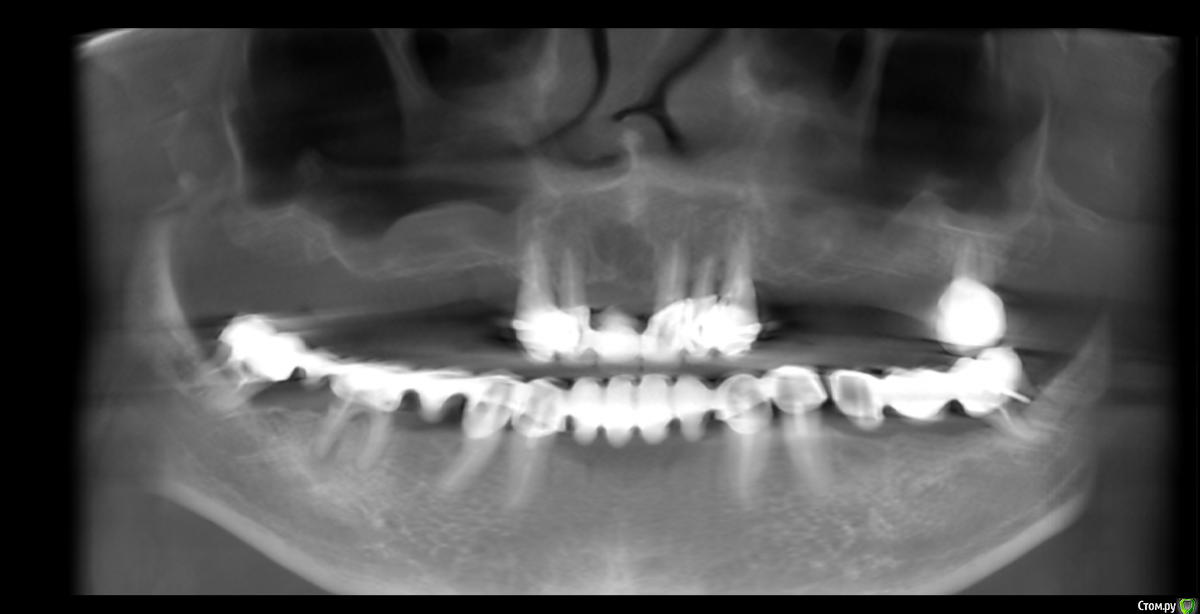

Irouil Опубликовано 29 июля, 2020 Поделиться Опубликовано 29 июля, 2020 На первый взгляд, удаление всех зубов тут не показано. Но надо составлять комплексный план протезирования и на его основе планировать имплантацию Ссылка на комментарий

Bier Опубликовано 29 июля, 2020 Поделиться Опубликовано 29 июля, 2020 Да вполне Allon4 тут подойдет. Не знаю никого из Воронежа к сожалению. Ссылка на комментарий

red_butler Опубликовано 29 июля, 2020 Поделиться Опубликовано 29 июля, 2020 Да вполне Allon4 тут подойдет. вроде синусы сразу за клыками начинаются... Ссылка на комментарий

Bier Опубликовано 29 июля, 2020 Поделиться Опубликовано 29 июля, 2020 вроде синусы сразу за клыками начинаются... дык транс-синус Ссылка на комментарий

Irouil Опубликовано 3 августа, 2020 Поделиться Опубликовано 3 августа, 2020 Я Вам рекомендую сначала сделать КТ челюстей и выложить его, а потом спросить рекомендации в нужной теме - потом уже решать куда и зачем ехать Ссылка на комментарий